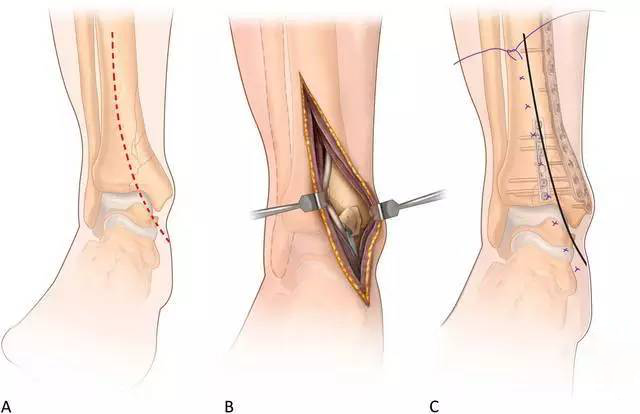

腓骨切口选择骨折平面切开,1/3 管型钢板固定。胫骨内侧 MIPO 切口:跨过内踝尖自近端前侧向远端后侧做斜行长约 3 cm(如图 3A)切口,该斜行切口允许延伸显露前方干骺端和关节面,能直接复位任何简单关节内骨折。

通过插入剪刀在软组织下、骨膜上建立通道,钢板远端拧入导向器当「把手」插入钢板(如图3B),皮外触摸可以评估钢板行进方向。

钢板远端位置:至少占据内踝的1/2,但最远不超过内踝尖,C 臂透视确定位置后克氏针临时固定,近端小切口显露钢板近端,同时必须确保骨折复位,触摸或 C 臂机透视确定后克氏针临时固定近端钢板。

C 臂机透视确定踝关节前关节面的复位情况:若复位满意,在植入非锁定螺钉时需要注意维持骨折的复位,因使用非锁定螺钉时可能导致钢板未贴合骨面处的骨折移位;若复位不满意,拧入一枚非锁定「复位」钉间接复位骨折(如图 3C)。

钢板远近端拧入锁定钉,骨折区域不打钉(如图3D)。若使用复位钉,最后取出复位钉,避免过于接近骨折端,常规关闭切口。若内侧 MIPO 切口无法复位骨折时,可延伸切口行有限切开复位。

图3 前内侧 MIPO 入路